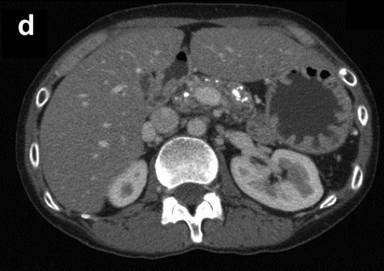

Figure 1. Abdominal enhanced CT in two patients with calcified chronic pancreatitis. a. b. Case #1. c. d. Case #2. |

In case #2, the patient was a 34-year-old woman who was diagnosed with alcoholic calcified chronic pancreatitis and a pancreatic pseudocyst six years ago. An infectious pancreatic pseudocyst was treated with pancreatic tail resection. Subsequently, she showed satisfactory improvement. However, the pain reappeared after she resumed drinking two years previously. Abdominal CT revealed a relatively large pancreatic stone in the main pancreatic duct in the pancreatic head (Figure 1c) as well as small diffuse stones in the pancreatic body (Figure 1d). She was started on an oral elemental diet at home.